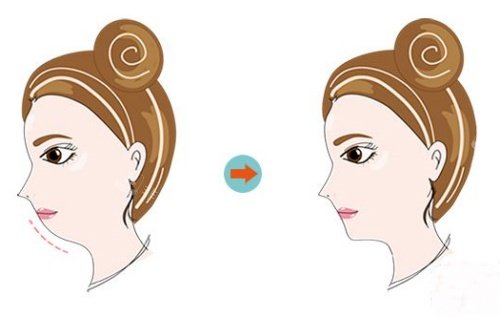

面部轮廓的改变则是意料之外的惊喜。因下颌骨不对称导致的面部偏斜问题得到了精又准改善,下颌线变得流畅自然,两侧脸颊的饱满度也趋于一致,不再需要靠厚重的刘海或侧分妆容刻意遮挡。这种改变并非刻意的“整容感”,而是基于骨骼生理结构调整的自然优化,让面部比例与五官特征更契合。

比外在改变更重要的,是心理状态的转变。术前因面部的不对称和咬合的困扰,我在社交场合中总是下意识地低头或侧过脸,甚至不敢大声说笑,怕别人注意到我的面部问题。如今能坦然直面镜头,和朋友聚餐时也能毫无顾忌地品尝各类食物,这种由内而外的自信感,是术前从未有过的。

在修养过程中我也逐渐明白,正颌手术的核心价值在于功能重建,解决颌骨的生理错位问题,面部轮廓的改善只是功能修复后的附带正向成效。这也让我更加确认,当初的选择并非单纯追求外在的改变,而是为了解决长期影响生活质量的健康问题。